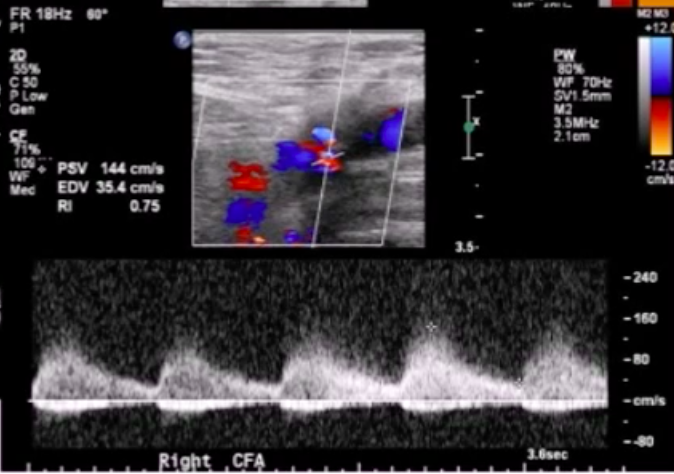

Cardiologist notes a femoral bruit a few days after performing transfemoral LHC. He calls you asking how likely you are to accurately diagnose a pseudoaneurysm (PSA) w/ DUS imaging.

What to tell him?

DUS is a both sensitive and specific for PSA diagnosis